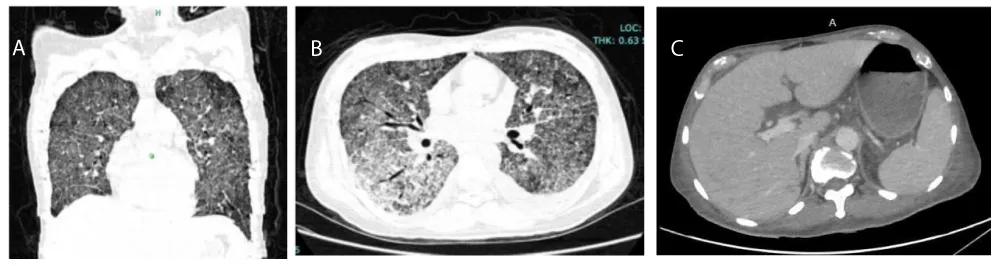

Bone marrow biopsy demonstrated increased histiocytes with hemophagocytosis, raising the HScore to 229 (97.8% probability of HLH). Axillary lymph node biopsy revealed chronic necrotizing, non-granulomatous lymphadenitis without malignant infiltrate, and acid-fast staining was negative. Etoposide (50 mg/m², dose-adjusted for hepatic function) was started to control immune dysregulation. Despite therapy, the patient developed hospital-acquired pneumonia and expired from septic shock (Figures 1,2) [Tables 1,2].